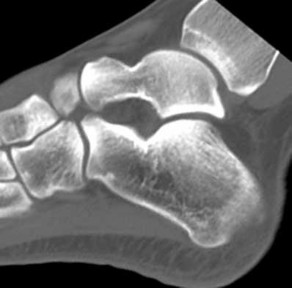

Figures 1a through 1c

Calcaneonavicular (CN) coalition

Talocalcaneal (TC) middle facet coalition

Tarsal coalitions occur when primitive mesenchymal cells fail to differentiate and form the

normal articular separations between the tarsal bones of the hindfoot. Overall incidence is difficult to determine because many affected people are minimally symptomatic or asymptomatic. Symptomatic tarsal coalitions typically present in adolescents as a painful flatfoot; however, there are a number of possible presentations, and occasionally symptoms do not appear until adulthood. Most tarsal coalitions are between the calcaneus and the navicular (CN) and the talus and the calcaneus (TC). Although most TC coalitions are across the middle facet, posterior facet coalitions do occur. Plain radiographic evaluation of suspected tarsal coalition is the mainstay for diagnosis. However, coalitions can be bony or fibrous, and making the diagnosis can be difficult. The addition of CT images to distinguish bony definition and MR images to decipher soft tissue can aid in diagnostics. Bony coalitions appear as definite bony bridging between the bones, while fibrous coalitions are suspected when distortion of the bony anatomy is seen. Bony coalitions are best seen on the oblique view (CN) and Harris axial view (TC). There are a number of secondary signs such as the anteater (AE) sign (elongation of the anterior process of the calcaneus as it extends to the navicular as seen on the lateral view [CN]). talar beaking (traction spur of the talar neck thought to result from abnormal stresses as seen on the lateral view [both CN and TN]), and the “C” sign (a continuous cortical contour from the medial talus to the sustentaculum tali [ST]) as seen on the lateral view (TC). A number of newer signs are not as well known, such as a broad mediolateral dimension of the navicular on the anteroposterior (AP) view (the

navicular is wider than the talar head [CN]), nonvisualization of the middle facet on the lateral view (TC), the brick sign (a normal ST is flat, but a distorted ST is enlarged and curved [CN]), and a tapered lateral navicular bone as seen on the AP view (the medial navicular [CN] is much thicker than the lateral navicular).

Figure 1a shows talar beaking (TB), an AE, and an open middle facet (MF). Figure 1b shows a wide navicular (WN), and Figure 1c shows an abnormal articulation between the calcaneus and the navicular, all consistent with a CN coalition.